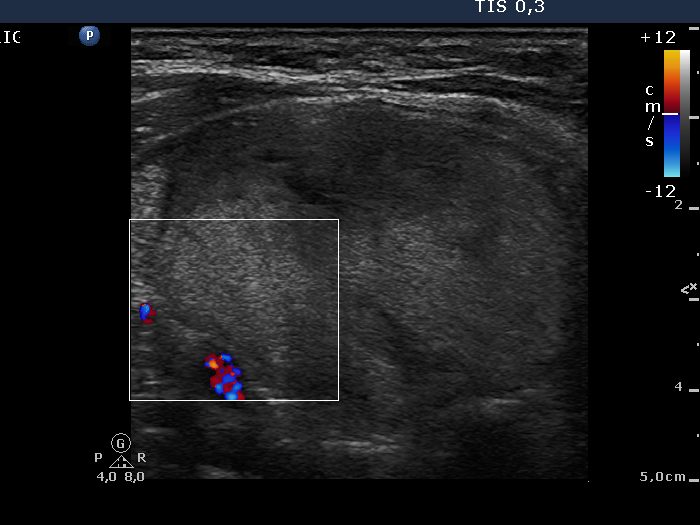

Right lobe, longitudinal scan

Left lobe, horizontal scan, color Doppler mode. The vascularization is decreased.